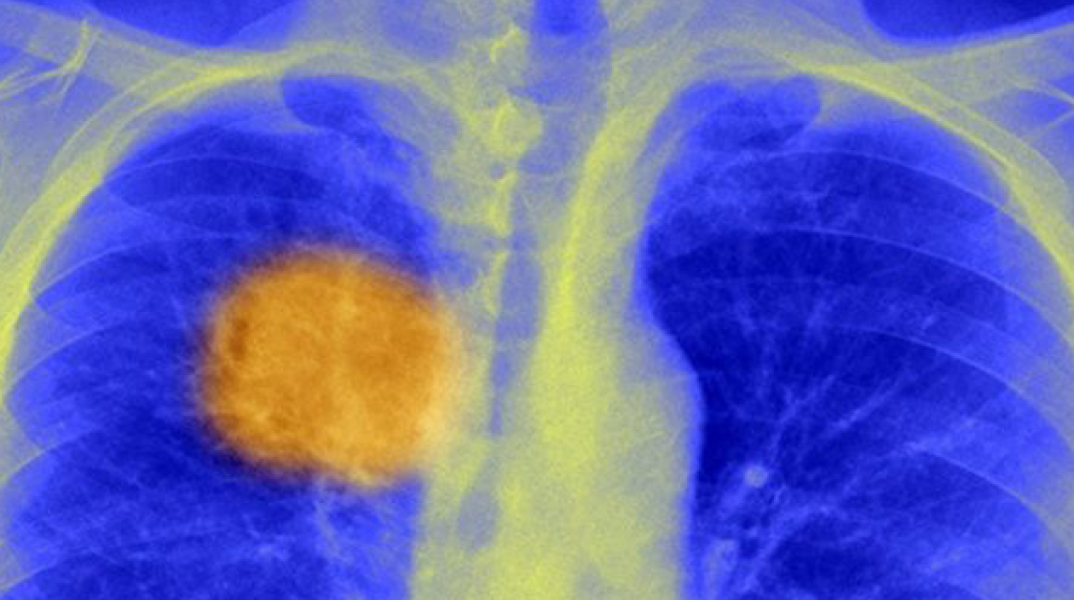

Κοντά στην «αχίλλειο πτέρνα» του καρκίνου

Μια επανάσταση που όμως έχει υψηλό κόστος και δεν έχει δοκιμαστεί κλινικά

Επιστήμονες στη Βρετανία και στις Ηνωμένες Πολιτείες πιστεύουν ότι έχουν ανακαλύψει ένα τρόπο για να «οδηγήσουν» το ανοσοποιητικό σύστημα να εξουδετερώνει τους καρκίνους.

Οι ερευνητές στο πανεπιστήμιο UCL του Λονδίνου ανέπτυξαν ένα τρόπο να εντοπίζουν τα ευάλωτα σημεία του κάθε όγκου −την "αχίλλειο πτέρνα" του− ώστε στη συνέχεια να μπορεί μόνο του το ανοσοποιητικό σύστημα να χτυπήσει την ασθένεια. Οι επιστήμονες εκτιμούν ότι για πρώτη φορά έχουν ενδείξεις ότι μερικοί τουλάχιστον καρκίνοι φέρουν πάνω τους τούς σπόρους της καταστροφής τους. Ωστόσο, αυτή η εξατομικευμένη μέθοδος θεραπείας κάθε ασθενούς έχει υψηλό κόστος και δεν έχει ακόμα δοκιμαστεί κλινικά.

Οι ερευνητές εκτιμούν ότι αναλύοντας το γενετικό υλικό (DNA) του κάθε καρκινοπαθούς, μπορούν να αναπτύξουν στοχευμένες προσωπικές θεραπείες, που θα καθοδηγούν με ακρίβεια τα αμυντικά κύτταρα του σώματος σε συγκεκριμένους ευάλωτους στόχους πάνω στους καρκινικούς όγκους. Αυτή η επαναστατική ανακάλυψη δημιουργεί την ελπίδα ότι η νέα γενιά των υπό ανάπτυξη ανοσοθεραπειών θα είναι πραγματικά προσαρμοσμένη στην ιδιαιτερότητα των όγκων κάθε ασθενούς, ώστε να είναι αποτελεσματική.

Η νέα θεραπεία αναμένεται να εφαρμόζεται σε συνδυασμό με υπάρχοντα φάρμακα, που εμποδίζουν τους καρκίνους να εξουδετερώνουν τα Τ-κύτταρα του ανοσοποιητικού συστήματος. Οι επιστήμονες δημοσιοποίησαν την έρευνα τους στο περιοδικό «Science».